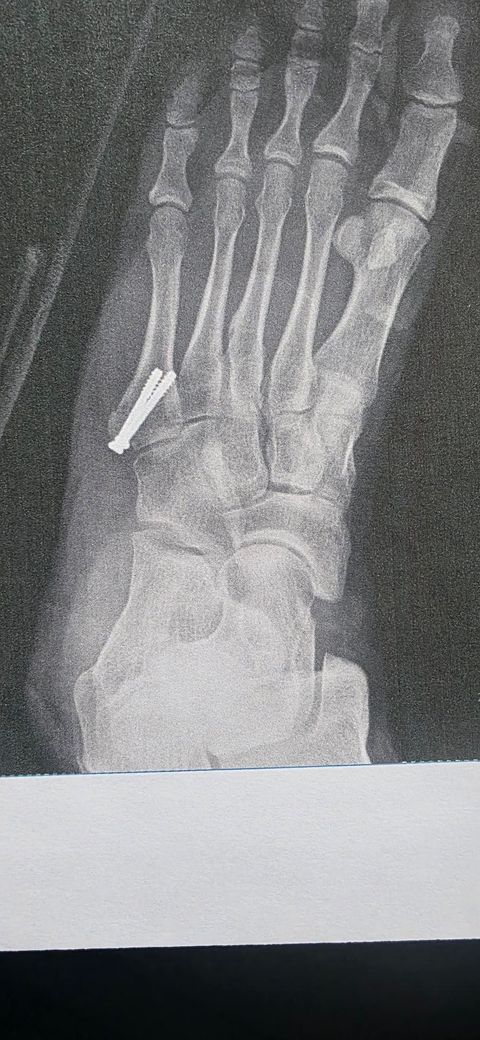

작년 01월에 사진과 같이 새끼발가락 발등쪽에 뼈가 살짝 떨어졌다고 해서 핀을 박았습니다.

사진은 수술직후 사진입니다.

• 1번 째 사진